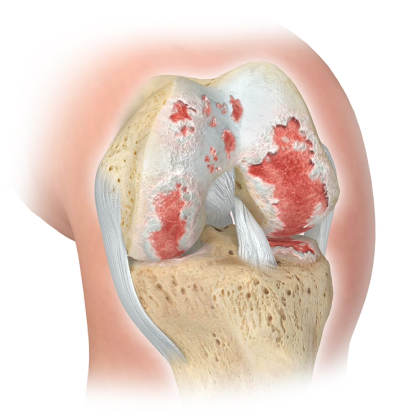

A prótese do joelho nada mais é que um recapeamento da articulação do joelho por implantes metálicos e sintéticos que envolvem os ossos desprotegidos de sua estrutura de proteção nativa (cartilagem). Serve, portanto, para aliviar as dores causadas pela artrose (doença do joelho que elimina / degenera a cartilagem) em condições avançadas. Um joelho que tem artrose avançada dói muito quando usado já que os nossos ossos são vivos e têm nervos que levam o joelho a doer quando perdem sua proteção natural de menisco e cartilagem

Ver mais sobre Artrose